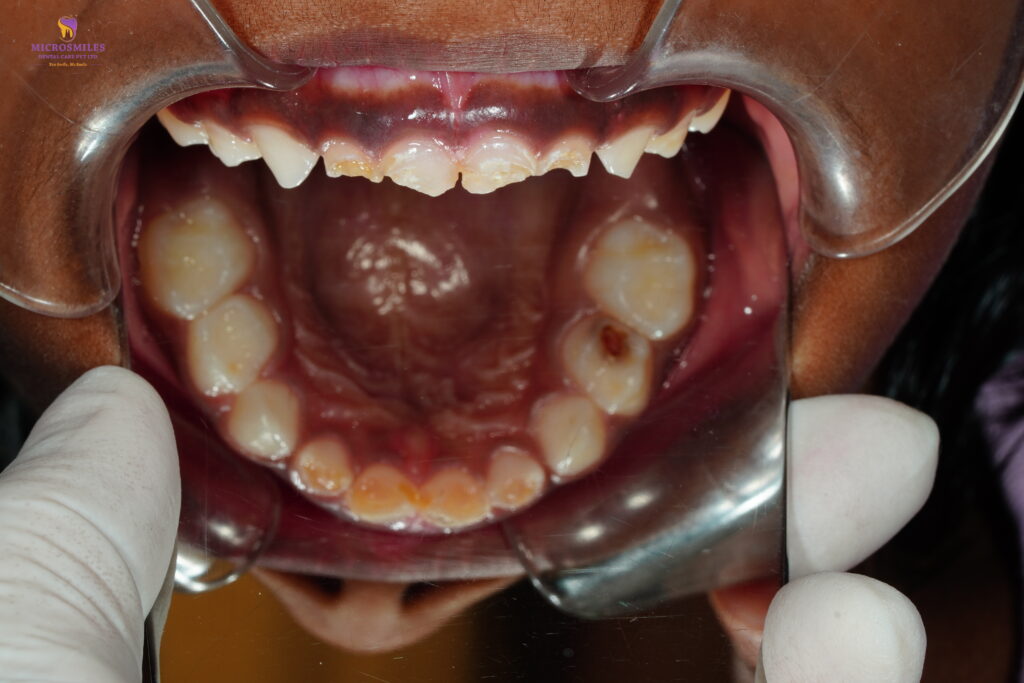

When your child has a severely decayed or infected baby tooth, removing it isn’t always the best option. At Microsmiles Dental Care, our pediatric specialists offer Pulp Therapy (Kid’s Root Canal)-a safe, effective way to save baby teeth, relieve pain, and maintain proper dental development.

Pulp therapy is often called a “baby tooth root canal.” It involves removing the infected or inflamed part of the nerve (pulp) while preserving the rest of the tooth. It’s typically followed by a protective crown-allowing your child to chew, speak, and smile pain-free.

This treatment is ideal when: